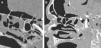

MethodsA descriptive study was performed including CT images of 20 cadaver heads. The specimens were perfused with a radiopaque material and various anatomical parameters were analysed.

ResultsThe anterior ethmoidal artery was found in 95% (38/40) of cases. It originated from the ophthalmic artery in 87.5% (34/40) of nasal cavities. In six cases, normal variants were found. The mean length of the anterior ethmoidal canal was 8.43±0.74mm. The angle performed into the skull base was 37.3±5.48°. In 90% of cases (36/40), it was located between the second and third lamella. The posterior ethmoidal artery was localised only in 14/40 cases, with 28.5% (4/14) of them showing normal variants. The mean length of the posterior ethmoidal canal was 7.1±1.02mm. The angle performed into the skull base was 7.11±4.07°. The distance from sill to the anterior ethmoid artery was 55.51±5.52mm. The angle between the nasal spine and the anterior ethmoidal canal was 57.67±1.68°. The distance between the nasion and the anterior ethmoidal canal was 29.31±2.53mm, the distance was 11.24±2.14mm from the anterior ethmoid artery to the posterior ethmoid artery and from the posterior ethmoid artery to the optic nerve, 7.26±1.33mm. Supraorbital cells were observed in 15% (6/40) of the cases.